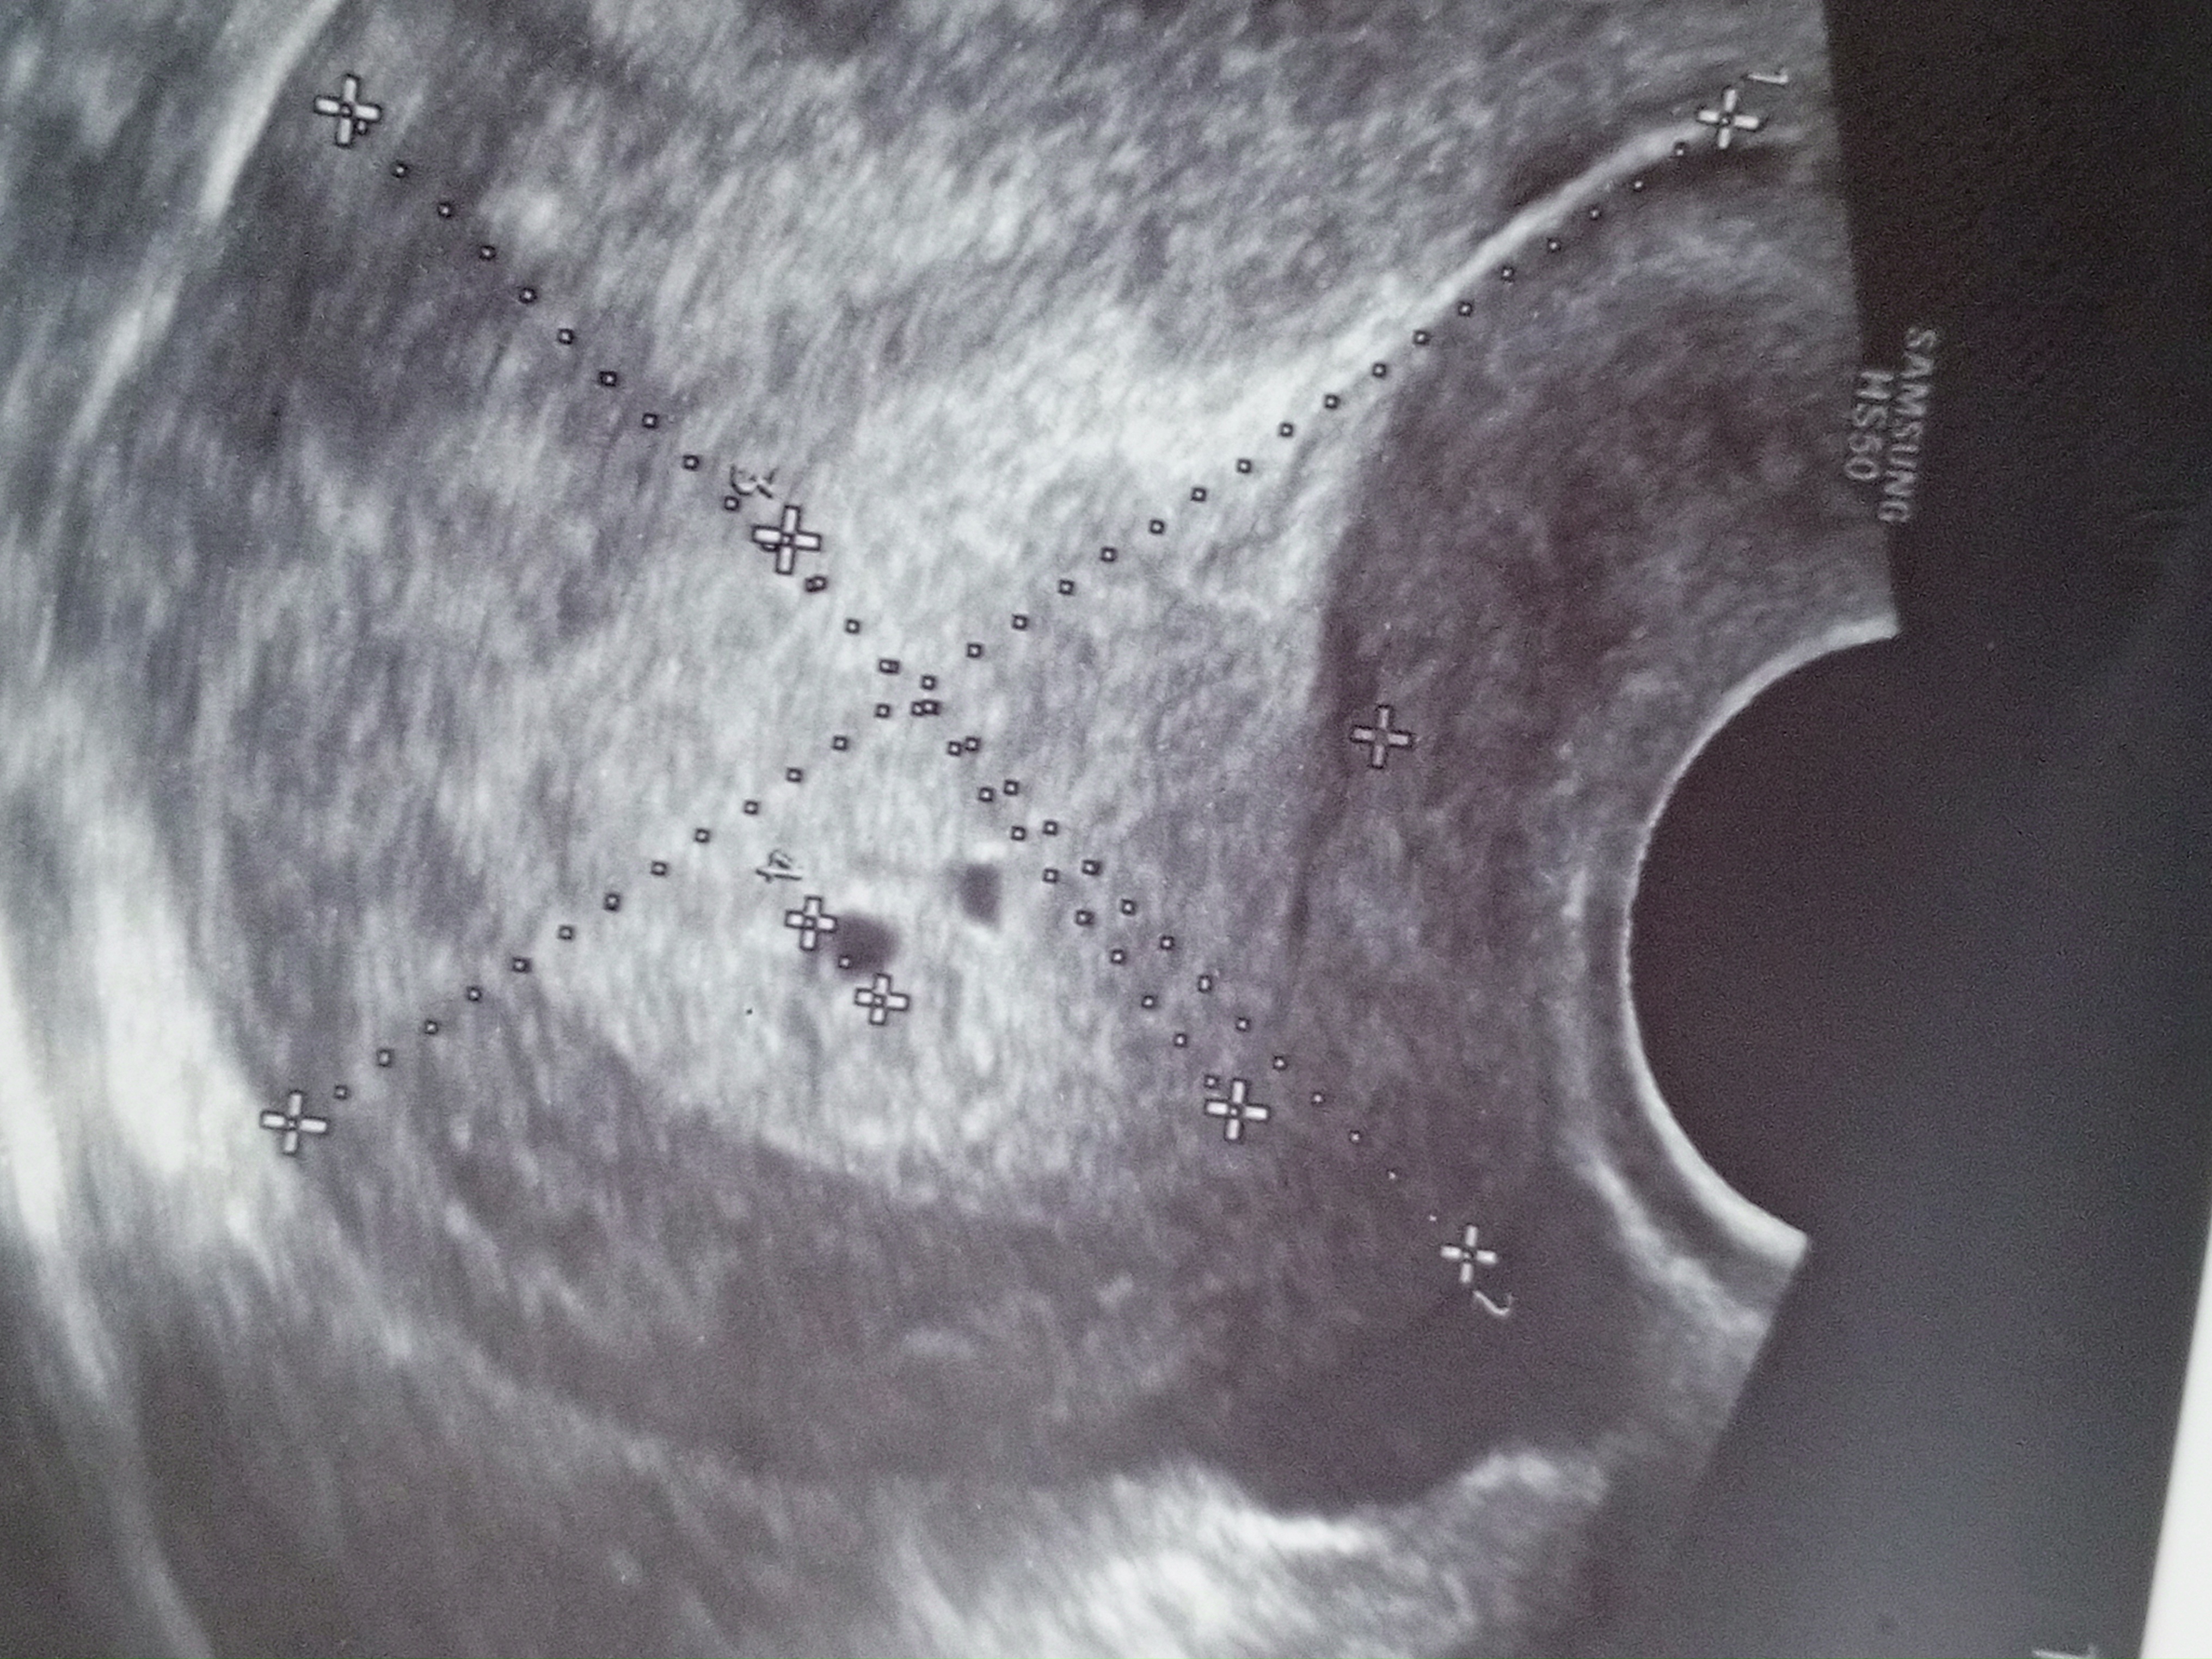

Узи 20 дпо

УЗИ, КТГ, доплер, скрининг, ХГЧ и другие анализыСделала узи 20 дпо, описали одно плодное яйцо, у гинеколога спросила она сказала что второе тоже похоже на яйцо но через неделю уже точно видно будет

Но с большей долей вероятности что беременность одноплодная сказали, у кого как было?